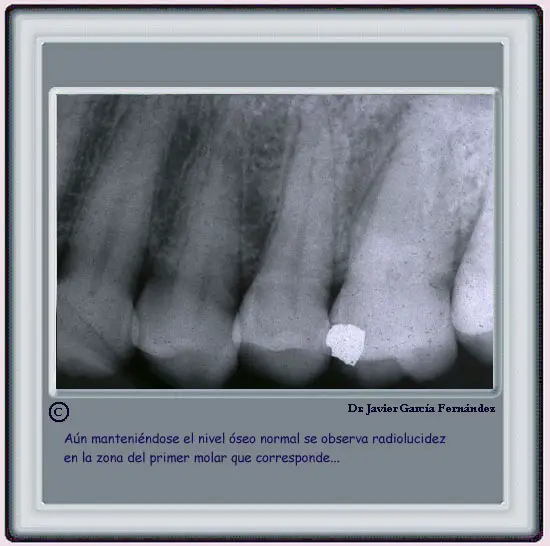

EXAMEN RADIOLOGICO